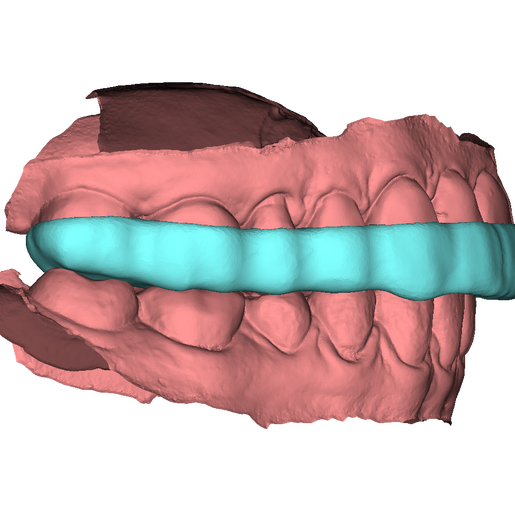

DSD Bite Splint Design

The DSD Bite Splint (night guard) is designed to be worn after a full mouth rehabilitation to protect DSD Natural Restorations and/or DSD Direct composite restorations. The splint design can be used for both milling and printing.

This product is ideal when you need to protect restorations that have already been placed to help avoid possible fractures due to grinding and bruxism.

An .STL file of the DSD Bite Splint design that can be used for manufacture, either by DSD Lab or your local lab.